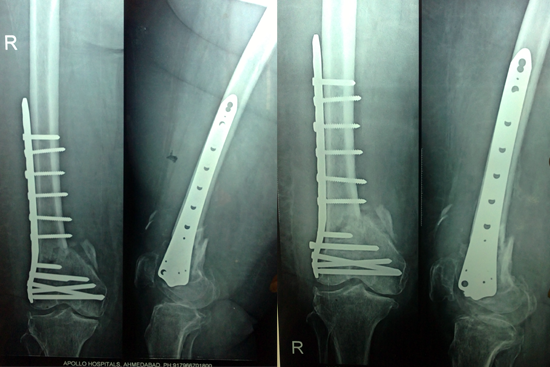

Non Union Femur

Case 1

Case 2 (Rampyari)